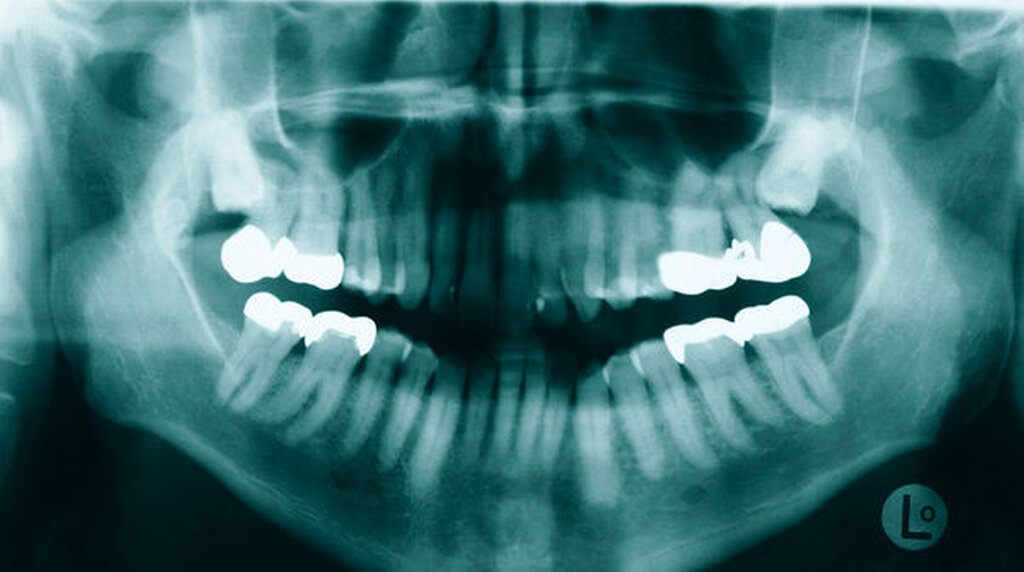

Zu erkennen waren im rahmenartig flankierenden Abschnitt des reifen Knochengewebes enthaltene Fettzellnester. Die äußere Begrenzung erschien undulierend, aber scharfkantig. Bestätigt wurde zudem die vollständige Exstirpation der Läsion. Die Histologie ergab eine Gewebsaussprengung atypiefreien Knochengewebes, das am ehesten mit einem ossären Choristom zu vereinbaren ist. Da Rezidive bei Choristomen nicht zu erwarten sind, erfolgte nach Nahtentfernung und Erstellung einer post-operativen PSA (Abbildung 4) keine Nachkontrolle mehr bei uns.